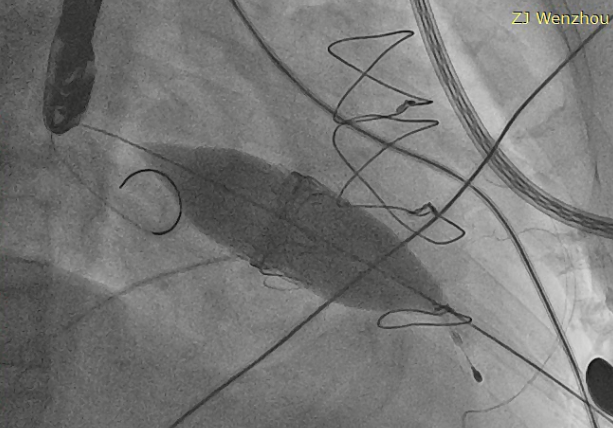

猪尾导管过瓣环平面进左心房

交换加硬导丝

扩张鞘预扩心尖穿刺点

输送器进入左室至生物瓣下方